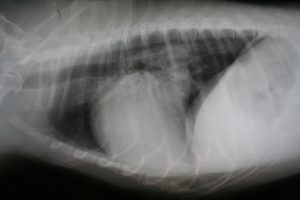

At Apple Lane Animal Hospital in Hutchinson, KS, we are proud to be on the cutting edge of medical technology. Radiology is a technique and diagnostic tool that we use to look inside the body in an entirely non-invasive way. X-rays allow us to create images of all the body’s organs.

In other words, the use of radiology gives us a view of the internal organs in your pet’s body that we otherwise could not see. It is a valuable diagnostic tool that helps veterinarians detect and prevent illness.